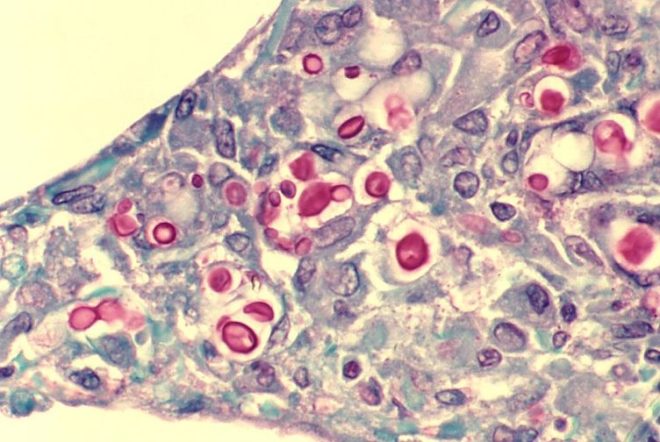

Грибковое заболевание криптококкоз

Большое количество дрожжевых грибов криптококков находится в помете голубя. Воздушно-пылевым путем и через нечищеные кондиционеры, используемые в быту, эти грибы попадают в жилище людей и способствуют их заражению криптококкозом.

Чаще всего подвержены заболеванию люди с ослабленной иммунной защитой.

Что происходит с человеком при заболевании криптококкозом:

- под действием грибов поражаются дыхательная система и головной мозг;

- в соединительной ткани легких образуются гранулемы;

- больного изнуряют сухой кашель и боль в грудине;

- если от инфекции пострадал мозг, больного тошнит и мучает головная боль.

Эта болезнь без надлежащего лечения опасна для жизни.